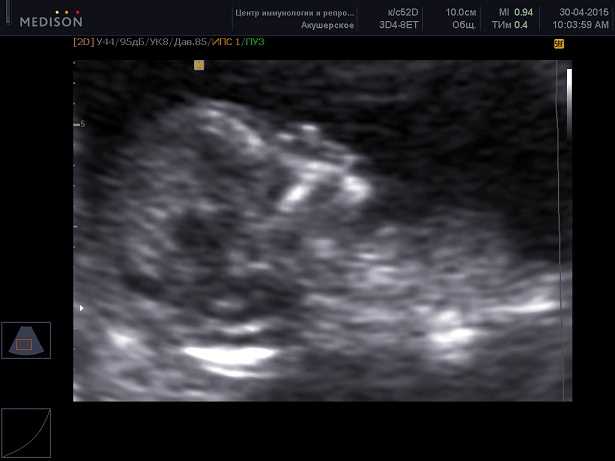

Сроки проведения скринингового узи обычно определяются исходя из особенностей развития и изменений организма в определенные периоды жизни. Так, скрининговое узи для беременных женщин обычно проводится в первом триместре (до 14 недель беременности), во втором триместре (между 18 и 22 неделями) и в третьем триместре (между 32 и 36 неделями). Эти сроки позволяют выявить врожденные аномалии и оценить рост и развитие плода.

Скрининговое узи — это обследование, которое проводится во время беременности для оценки риска развития определенных патологий или аномалий у плода. Во время скринингового узи врачи оценивают различные аспекты плода, такие как его размеры, структура органов, пульсация сердца и движения. С помощью скринингового узи можно выявить наличие некоторых врожденных аномалий, таких как спинальная грыжа, водянка головного мозга или сердечные дефекты.